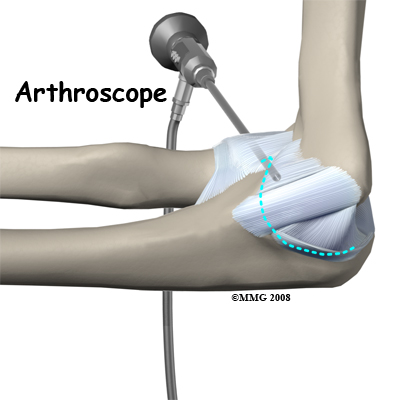

If you are having problems that may be coming from inside the joint, such as arthritis and loose bodies, your surgeon may perform an arthroscopy before the actual reconstruction procedure is done. During this procedure, a small TV camera is inserted into the elbow joint through two or three small (1/4 inch) incisions. Using special instruments your surgeon will be able to evaluate the joint, remove any loose bodies and bone spurs that may be causing problems. Arthroscopy is not always necessary.